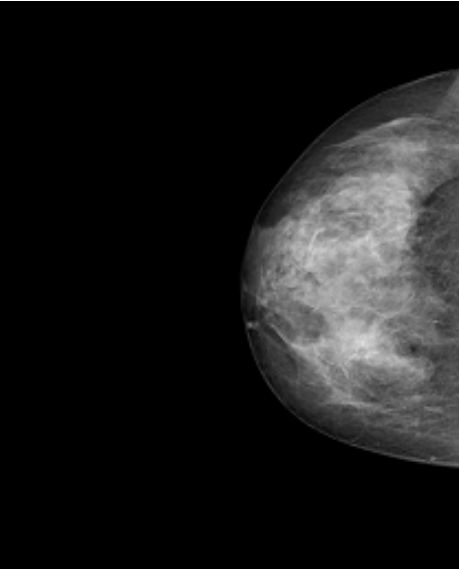

Datos Clínicos: Paciente Femenino de 58 años.

Diagnóstico: Calcificación Baja Sospecha Maligna.

Dimensiones: 632 x 548.